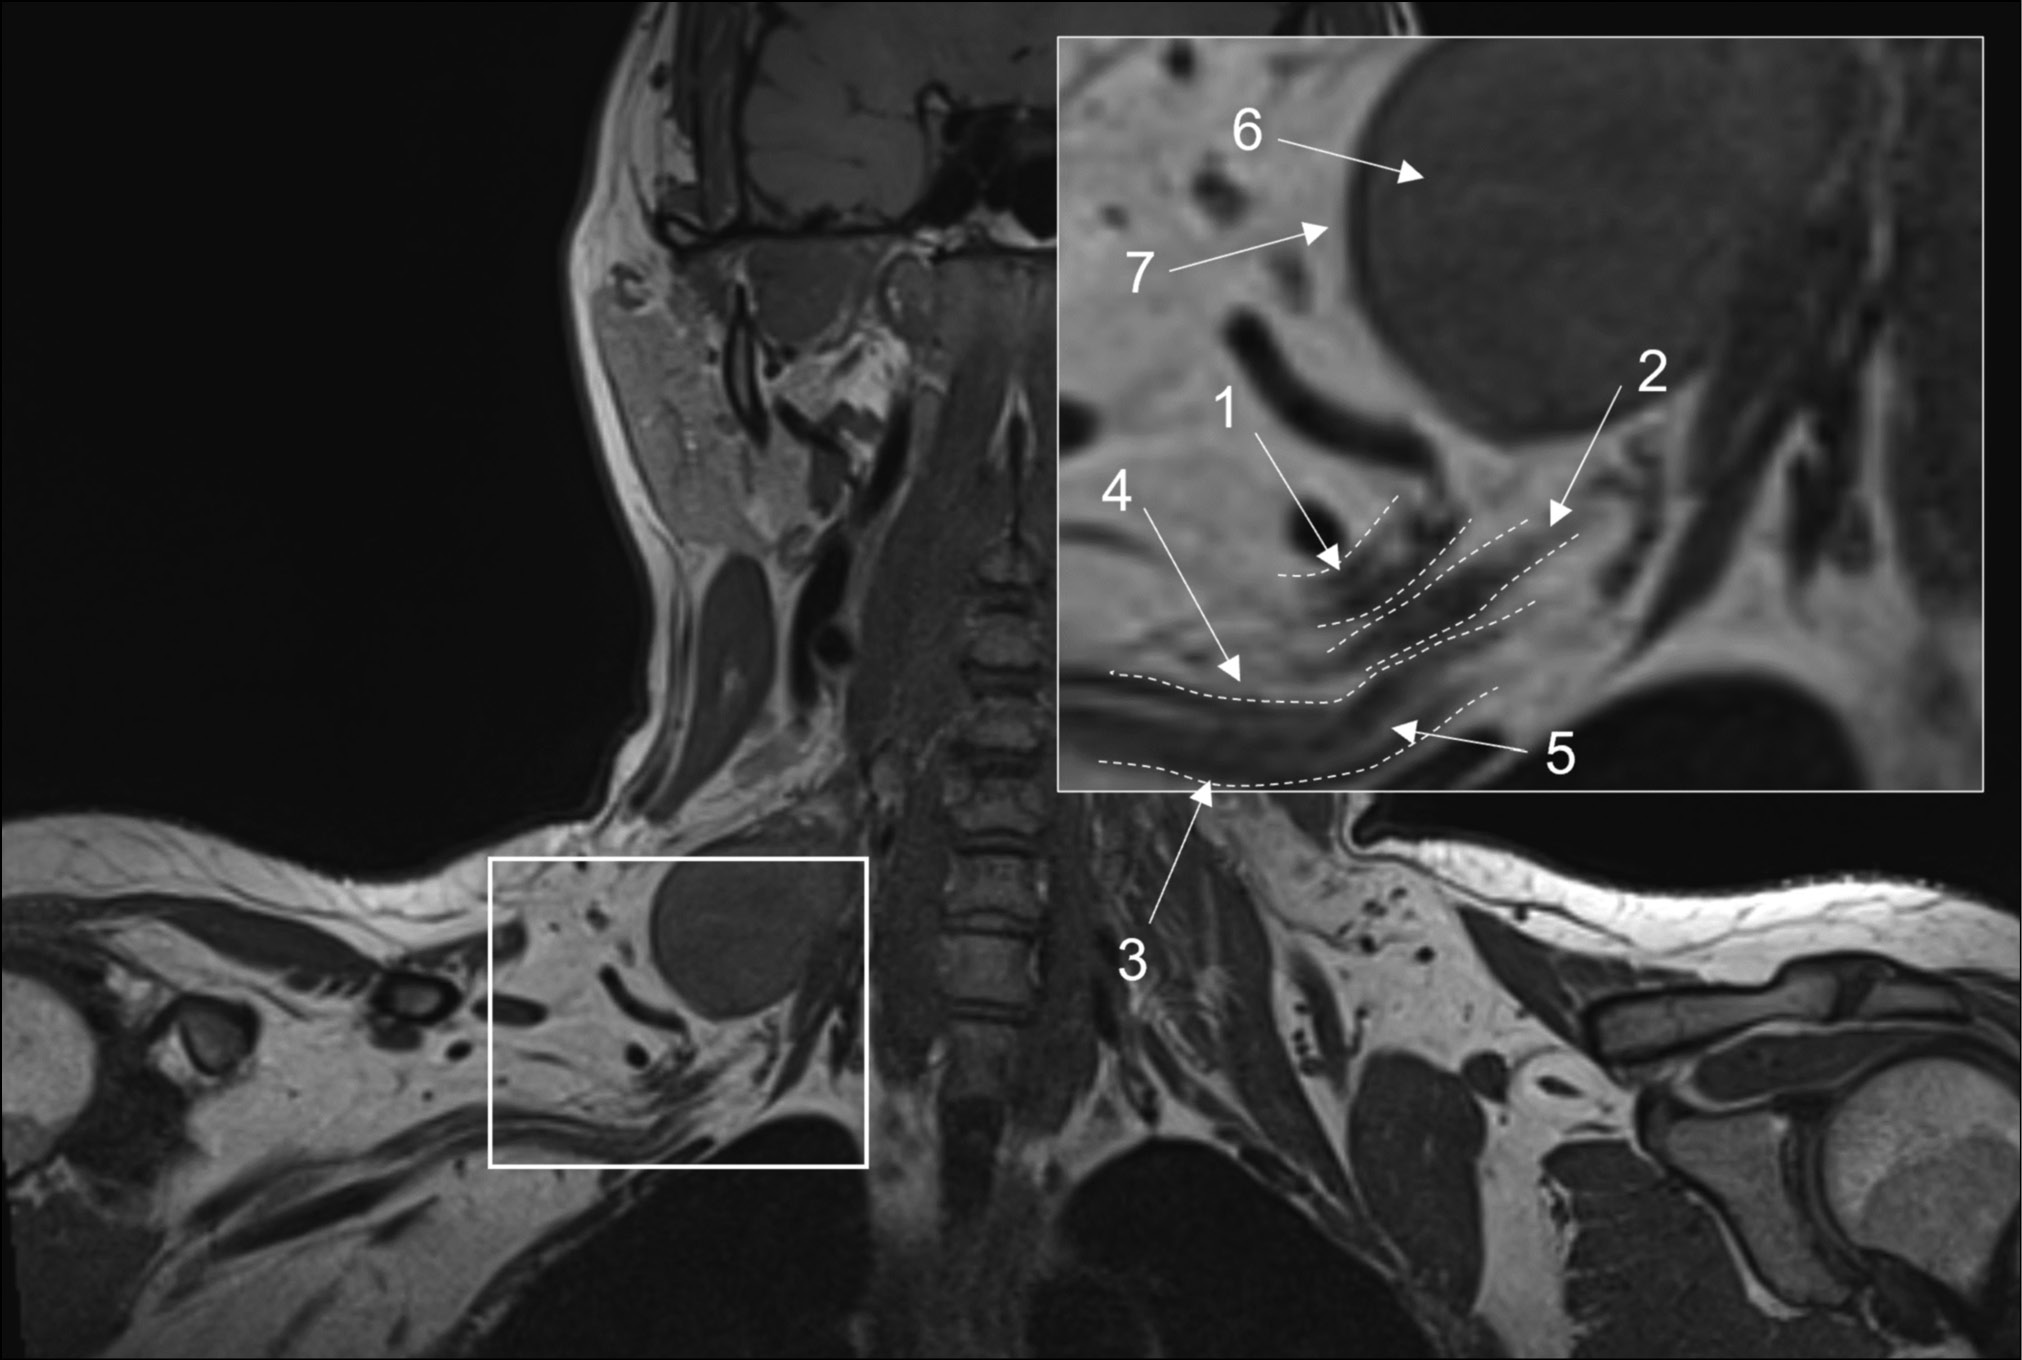

Fig. 1. Magnetic resonance imaging of the brachial plexuses in 3D-T1 mode. A coronal projection: (1) the upper trunk, (2) the middle trunk, (3) the lower trunk, (4) the perineural fatty tissue, (5) the endoneurial fat, (6) a mass lesion (schwannoma), and (7) the intact fatty tissue around the lesion.